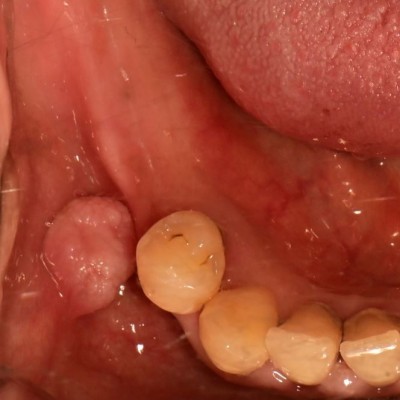

볼 안쪽 섬유종 제거 N새글 볼 안쪽 섬유종 제거입니다. 구강외과 전문의가 수술합니다. -----------------------------..